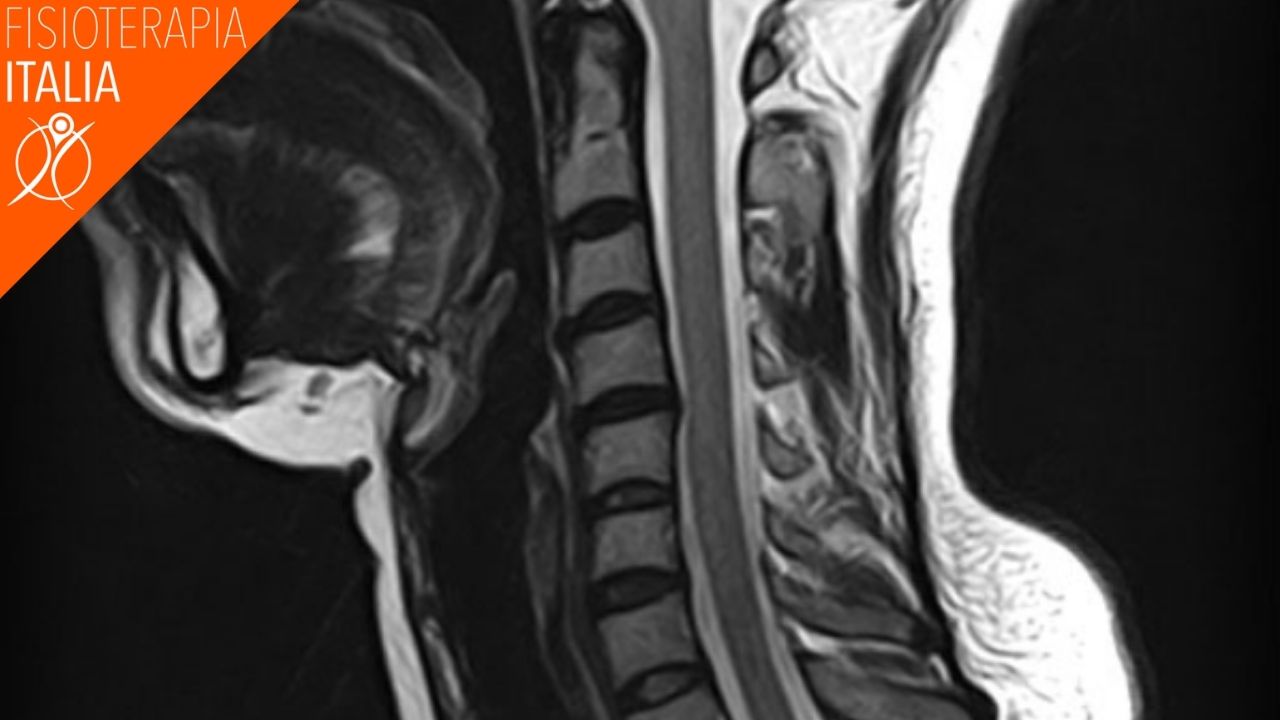

TEST DI IMAGING

Una lesione da colpo di frusta non è evidente nei test di imaging, ma il medico probabilmente ne prescriverà uno o più di uno per poter escludere altre condizioni patologiche.

I test di imaging includono: